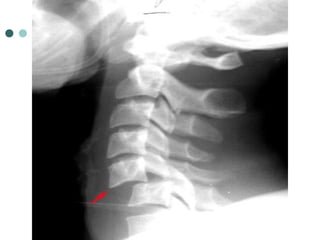

HANGMAN’S FRACTURE

 Fracture through the pedicle of C2 secondary to hyperextension

 Mechanism: Hanging or hitting a dashboard

 Best seen on lateral view

 Signs:

 Prevertebral soft tissue swelling

 Avulsion of anterior inferior corner of C2 associated with

rupture of the anterior longitudinal ligament

 Anterior dislocation of the C2 vertebral body

 Stability: unstable